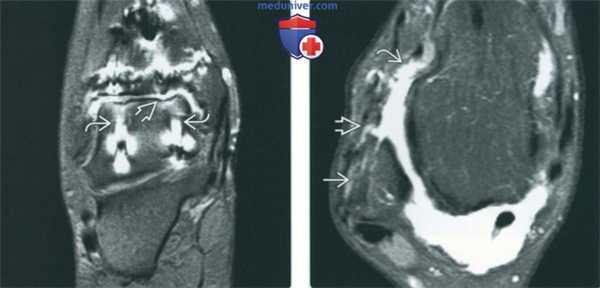

(Слева) МР-артрография в режиме Т2ВИ FS, коронарный срез, состояние после аллотрансплантации фрагментов большеберцовой и таранной костей: визуализируются обширные артефакты от винтов. Однако они не помешали выявить истончение суставного хряща, подтвержденное впоследствии при артроско-пии.

(Справа) МР-артрография в режиме PD FS, аксиальный срез, этот же пациент: в малоберцовой кости определяется туннель. Целостность проходящей в нем восстановленной связки нарушена, вследствие чего происходит затек контрастного препарата вдоль передней поверхности шейки таранной кости. (Слева) МР-артрография в режиме PD FSE FS, сагиттальный срез: в большеберцовой и таранной костях видны костно-хрящевые аллотрансплантаты. Заметна небольшая зона аваскулярного некроза. Головка винта выступает за суставной хрящ таранной кости. После удаления винта боли исчезли.

(Справа) МР-артрография в режиме Т1ВИ, сагиттальный срез: отмечается ровный контур фиброзного хряща, заполнившего коано-хрящевой дефект после высверливающей хондропластики. Зона реактивного склероза в подлежащей кости при всех последовательноаях характеризовалась гипоинтенсивным сигналом.

(Справа) МР-артрография в режиме PD FS, аксиальный срез, этот же пациент: в малоберцовой кости определяется туннель. Целостность проходящей в нем восстановленной связки нарушена, вследствие чего происходит затек контрастного препарата вдоль передней поверхности шейки таранной кости.

(Слева) МР-артрография в режиме PD FSE FS, сагиттальный срез: в большеберцовой и таранной костях видны костно-хрящевые аллотрансплантаты. Заметна небольшая зона аваскулярного некроза. Головка винта выступает за суставной хрящ таранной кости. После удаления винта боли исчезли.